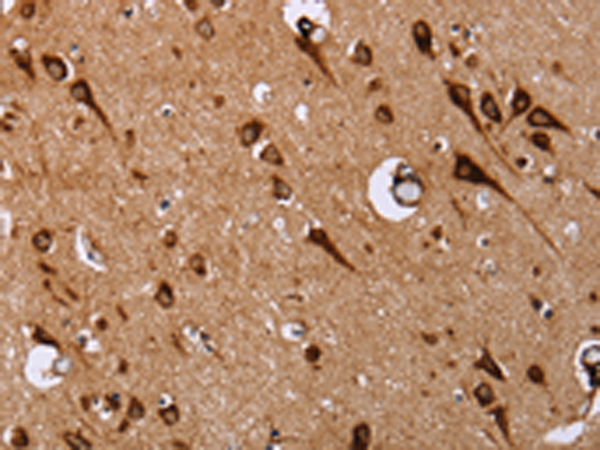

分类: 科研抗体货号: P08266别名: EF2; EF-2; EEF-2; SCA26应用: WB,IHC反应种属: Human, Mouse, Rat